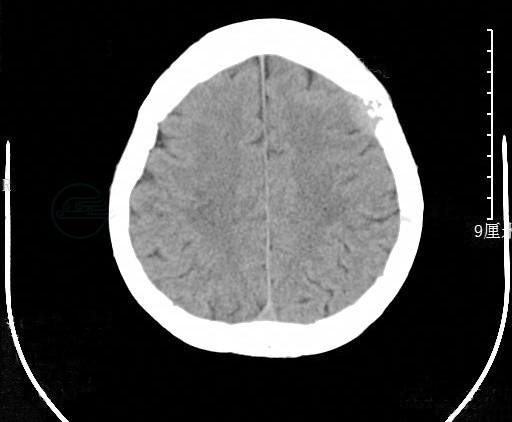

胸部CT:未见明显异常(图2)。

图2 胸部CT

胰腺MRI:胰腺体尾部稍饱满,所见椎体有多发骨质信号改变。